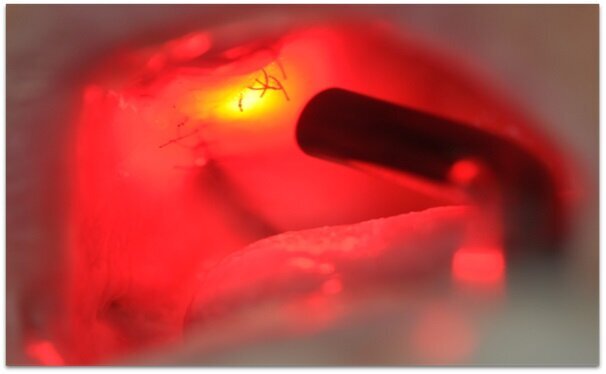

_3. Fotobiomodulacja – zewnętrznie, w miejscu zabiegu zastosowanie światła lasera diodowego Lasotronix® Smart M 635 nm, 3 J/cm2 na punkt przyłożenia, 25 s przez 2 tygodnie (3 razy w tygodniu). Po 2 tygodniach zdjęto szwy.

Ryc. 4_Śródzabiegowo: po chirurgii laserowej widoczna zdrowa tkanka kostna.